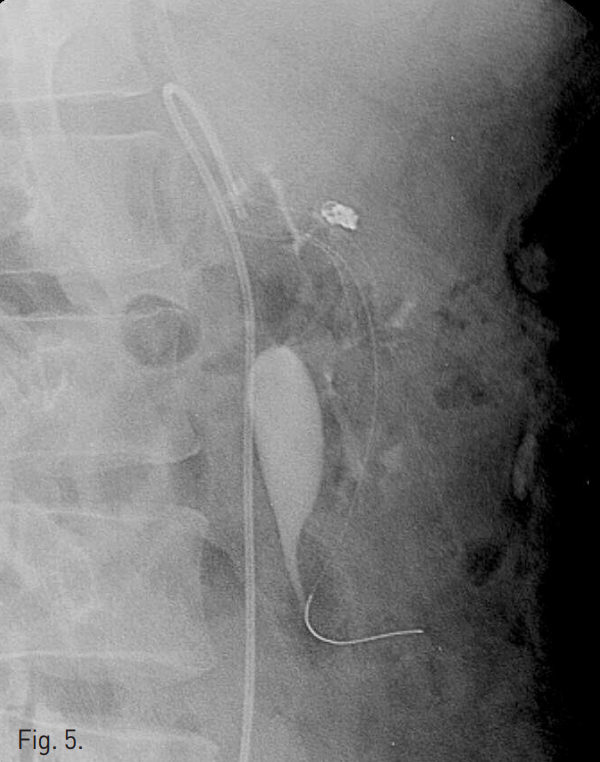

그 후 대퇴동맥을 통해 aneurysm내에 삽입했던 microcatheter를 통해 4mm x 2mm tornado microcoil (Cook, Bloomington, IN, USA) 4개를 사용하여 dissecting aneurysm 에 대한 stent assisted coil embolization을 시행하였다(Fig. 5).

Fig. 5

A radiograph taken after stent assisted coil embolization of dissecting aneurysm demonstrates coil packed aneurysm sac.